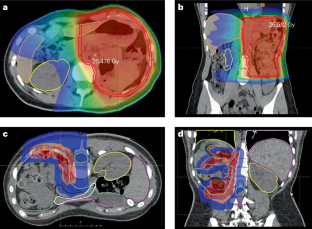

Janssens, G. O. et al. The SIOP–Renal tumour study group consensus statement on flank target volume delineation for highly conformal radiotherapy. Lancet Child. Adolesc. Health 4, 846–852 (2020).